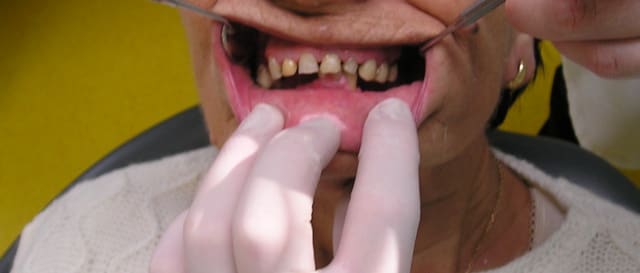

Et puisque lapin, une autre qui me fait plaisir, pourtant j'ai accumulé les boulettes sur celle-là...

J'attends encore 3 mois pour être certain de la cicatrisation de la 44 en distal avant les définitives, mais ça semble plutôt bien engagé.